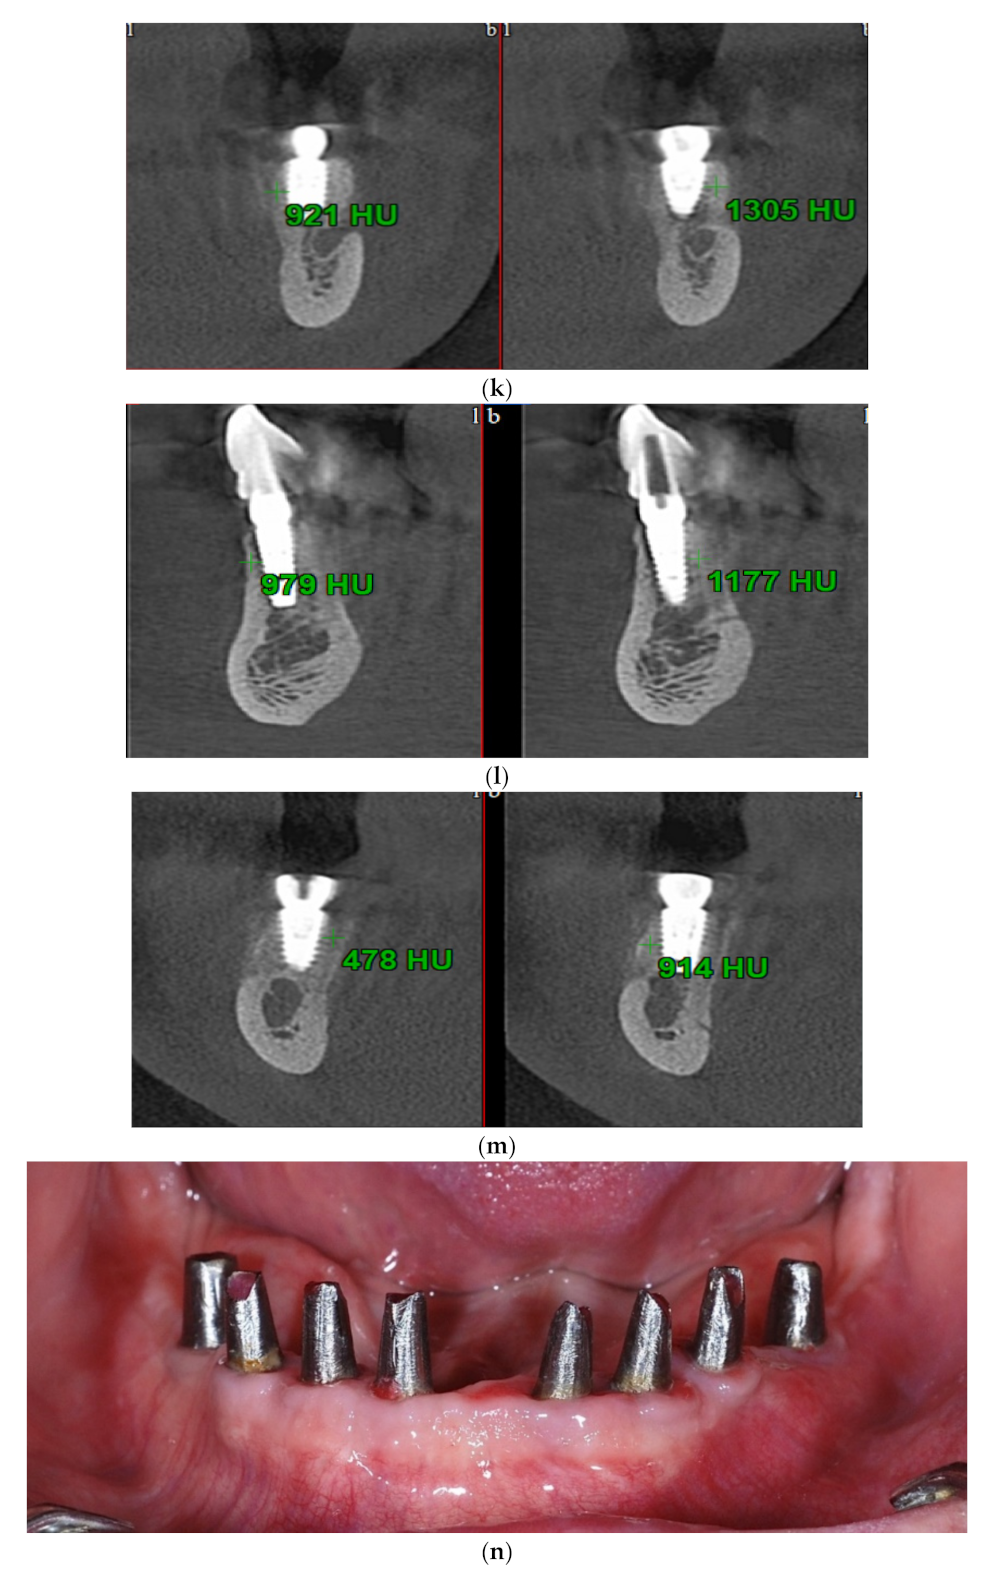

2.3. Evaluation of Clinical and Bone Parameters

3. Results